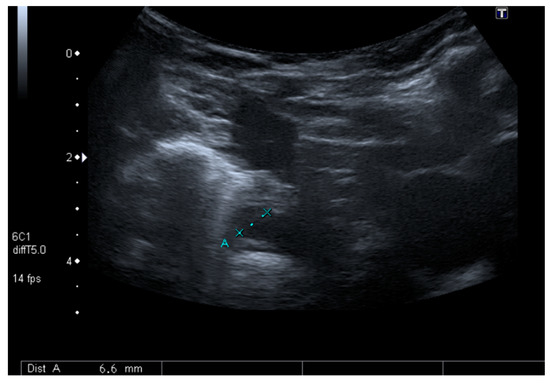

Although surgical drainage was considered, a follow-up CT scan showed a sustained decrease of the mediastinal lesions with antibiotics only. For this reason, the child was maintained under close surveillance with serial US (Figure 3). She maintained fever until the 6th day of antibiotics, after which a sustained clinical and laboratorial improvement was achieved. At the end of 4 weeks of IV antibiotics, the child was discharged without any symptoms and with complete resolution of the mediastinal lesions.

Figure 3. Follow up mediastinal ultrasound.